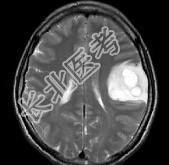

- 单项选择题女,33岁, 三个月前有右上肢及右颜面部麻木,伴耳鸣及头昏, 请根据所提供图像,诊断最有可能是 ( )

A、星形细胞瘤

B、脑血吸虫病

C、脑转移瘤

D、脑结核

E、脑脓肿